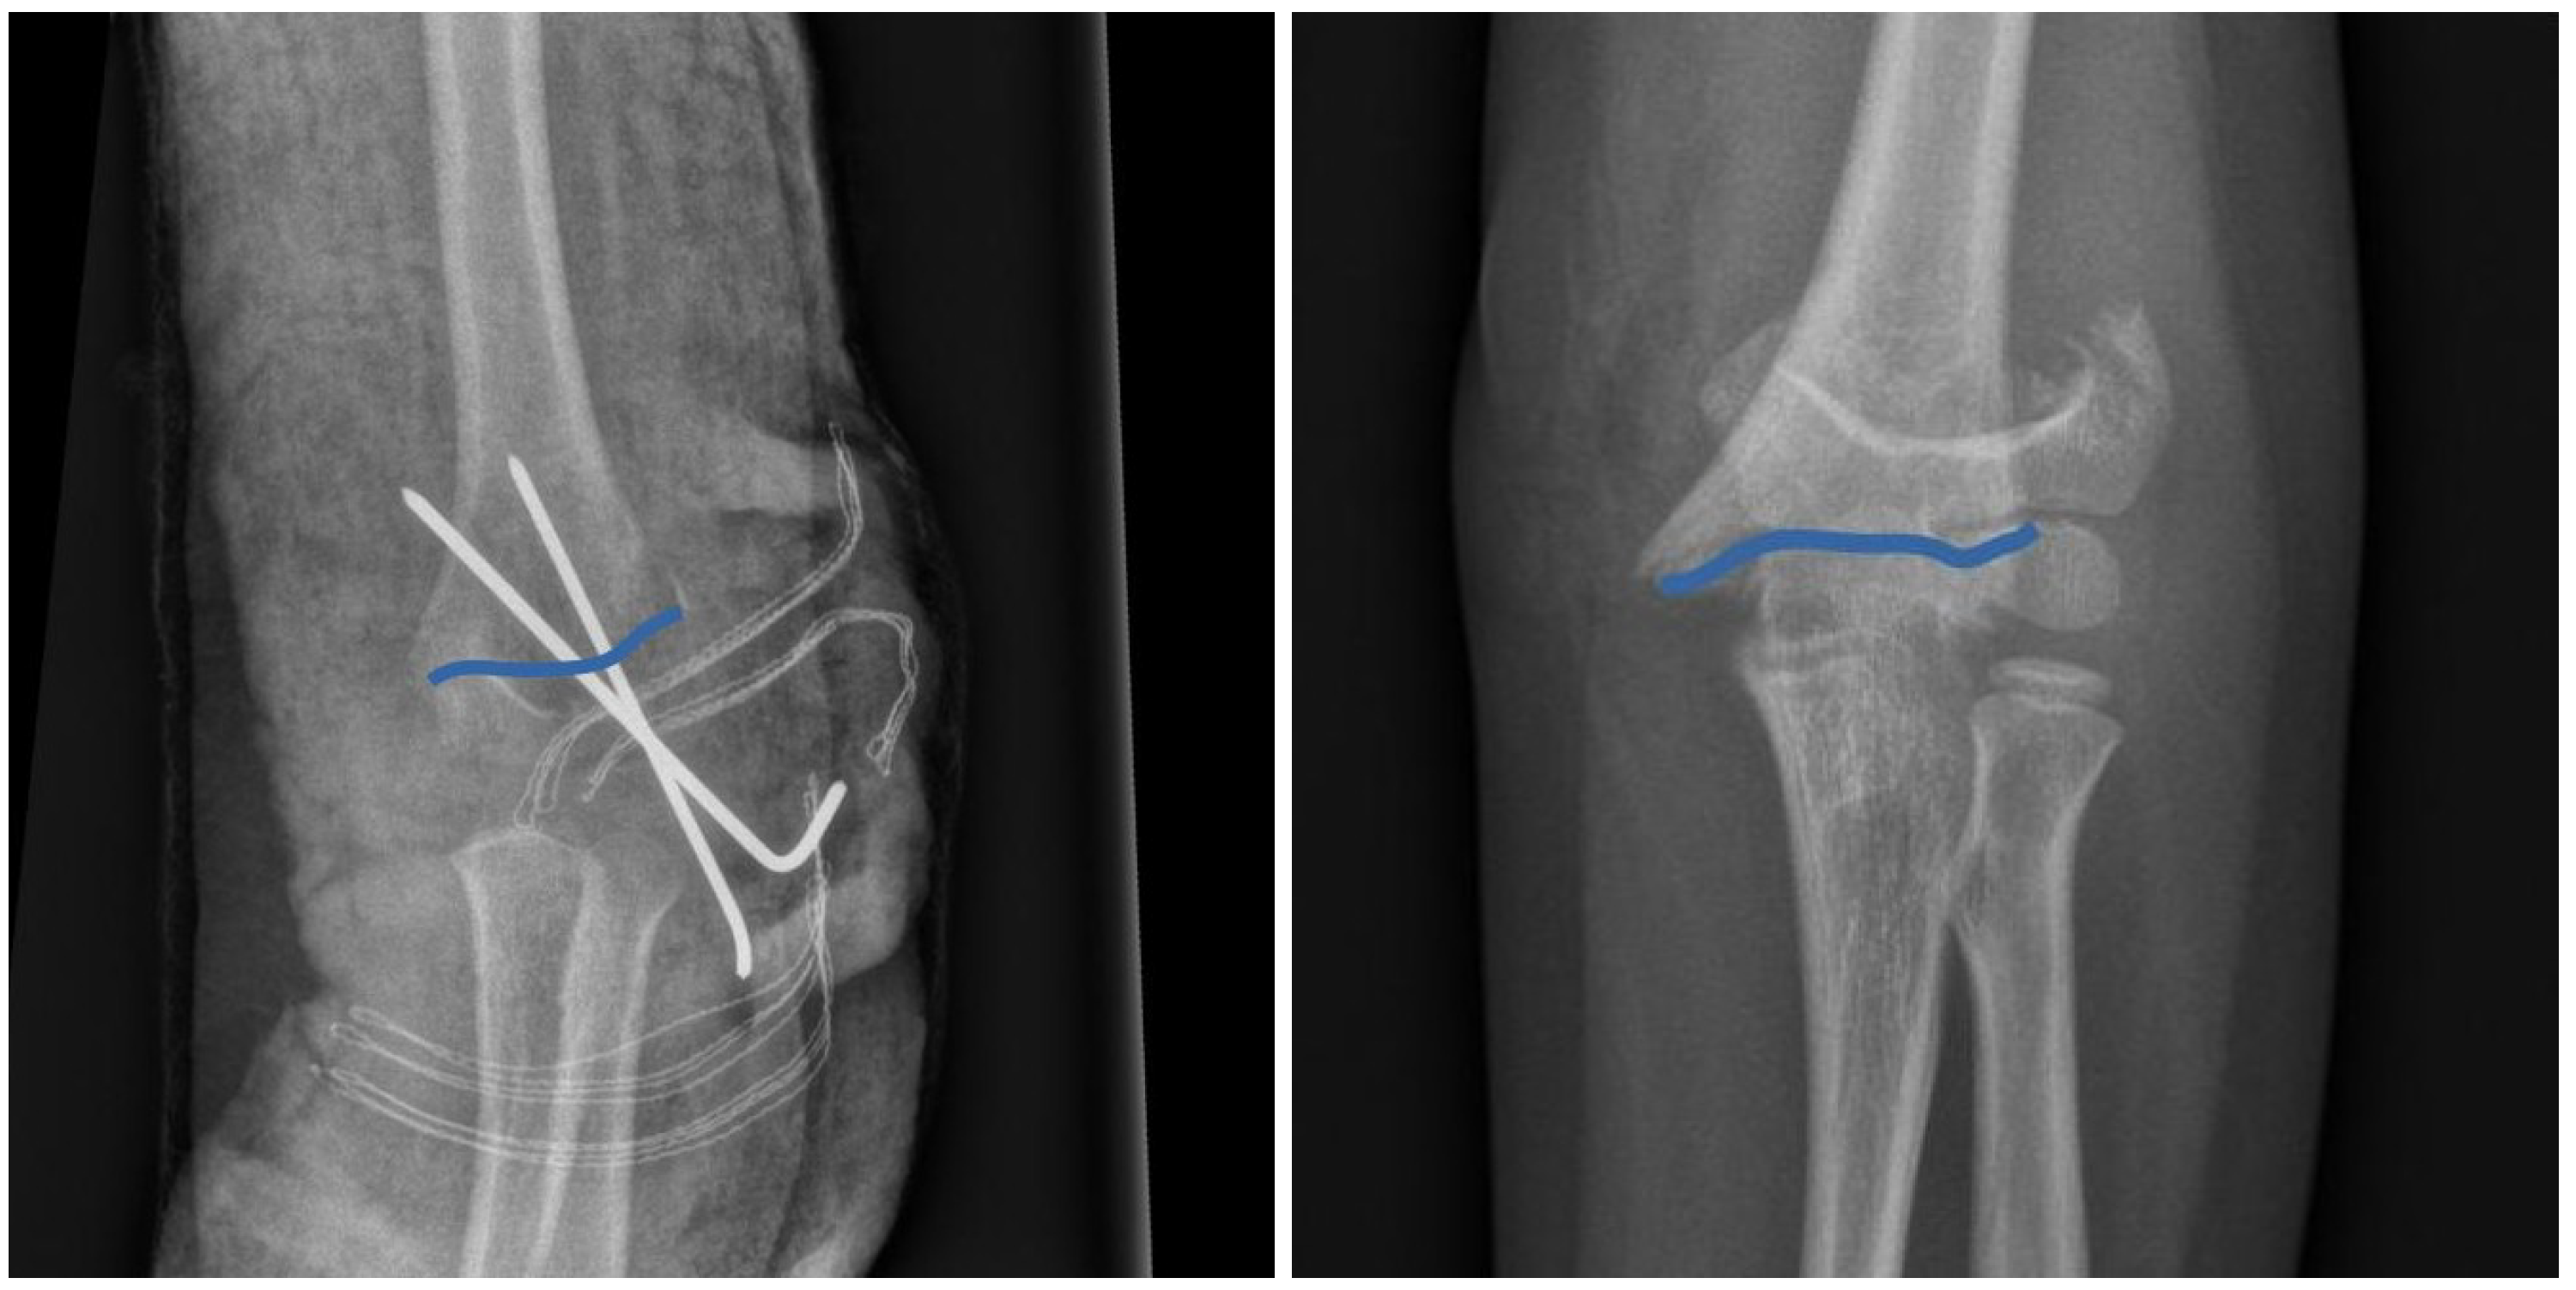

Figure 1. Examples of XR images of humeral fractures: from (AP) and side (L) projections. Solid lines indicate the fracture.

Our dataset comprises a total of 66 XR images in the anterio-posterior (AP) view and 24 XR images in the lateral (L) view, as illustrated in Figure 1. In our analysis, we employ a set of "scientific landmarks" (as defined in Ref. [27]) that constitute the shape of a fracture, as depicted in Figure 1. Specifically, we select 10 landmarks for each fracture. This approach of using a relatively large number of landmarks helps to mitigate potential biases that may arise from an expert’s subjective selection of specific landmarks. Consequently, our strategy ensures a quasi-random and uniform selection of landmarks. By digitizing the shape of a fracture using these scientific landmarks, our objective is to construct and analyze the mean shape for both the anterio-posterior (AP) and lateral (L) projections.

Our initial objective is to construct a mean (typical) shape for humeral fractures in both the anterio-posterior (AP) and lateral (L) views. In formal terms, a shape, denoted as X, belongs to a shape space M, which is a subset of the real Cartesian product, i.e., X M R 10 × 2 , where k = 10 represents the number of landmarks in each 2-dimensional image [27]. By identifying and selecting k = 10 scientific landmarks (as defined in Ref. [27]) from each XR image (66 in the AP view and 24 in the L view, as shown in Figure 1), we can construct a sample set of shapes, presented in the left panels of Figure 2, for both the AP and L views. The technical details of landmark extraction, utilizing Python’s "skimage" and Matplotlib tools, are summarized in the Methods section.

To ensure the utilization of open-source and freely available computational tools, we made a deliberate choice for our study. The initial preparation of images was conducted using the Python ’skimage’ package. Scientific landmarks for each fracture were extracted from the XR images, as shown in (Figure 1), using the ’FigureCanvasBase.mpl-connect’ method from the Matplotlib library. Procrustes analysis was performed using the ’shapes R-package and the ’procGPA’ function [30]. The landmarks used in our analysis can be accessed through the Data Availability Statement provided below.